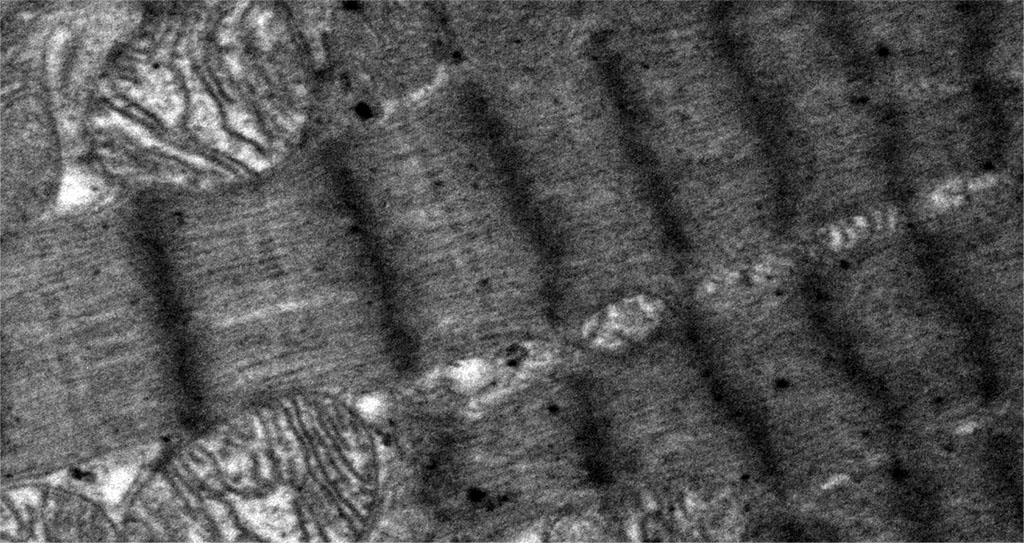

In some areas of contractile cardiomyocytes, the overcontractions of myofibrils were so pronounced that they led to the formation of areas of pronounced overcontraction or contractures (Figure 4), while these changes were absent in the control group. The visually recorded thinning of myofibrils in hypothyroidism may be due to a decrease in the formation of myosin protein in contractile cardiomyocytes, as reported in the molecular genetic study by N. Yousefzadeh et al, where the researchers reported a decrease in the expression of the myosin protein isoform characteristic of adults (heavy chain isoform alpha-myosin), in the myocardium of rats under conditions of hypothyroidism. A decrease in the expression of the adult myosin isoform was accompanied by a compensatory increase in the expression of the fetal myosin isoform (beta-myosin heavy chain isoform) and weakening of the contractile function of the heart, in particular, a decrease in the frequency and strength of heart contractions [27, 28]. Similar changes in the qualitative and quantitative composition of myosin protein isoforms and impaired contractile function were also noted in striated skeletal muscle tissue [29]. Hypothetically, it can be assumed that the change in the expression of the myosin protein is associated with the ultrastructural anomalies of the myofibrillar apparatus that we discovered. Contracture disorders of myofibrils, at the time of their formation, can be clinically manifested by cardiac arrhythmias, and subsequently lead to the loss of the ability to contract this area of the cardiomyocyte, which can lead to both a decrease in heart rate and a decrease in cardiac output. At the same time, hypothyroidism is indeed clinically manifested by similar myocardial symptoms [27]. Thus, the histopathological changes we found in the structure of the contractile apparatus are characteristic clinical signs of this endocrine nosology [30, 31].

Figure 4. Histopathological changes in the myofibrils of contractile cardiomyocytes. Areas of overcontraction of myofibrils of contractile cardiomyocytes with the presence of contractures. Magnification 6600. TEM.